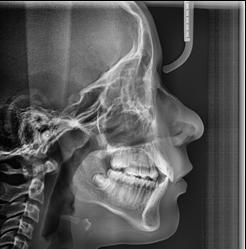

Figura 1. Radiografía inicial de la paciente. Se observa edentulismo total superior, a excepción del molar del primer cuadrante, indicado para exodoncia. En la mandíbula se aprecia pérdida ósea horizontal generalizada secundaria a la evolución de la enfermedad periodontal.

En la radiografía inicial (Figura 1) se observa la pieza 17 con pérdida ósea significativa, así como una reabsorción ósea homogénea a lo largo de todo el arco superior. En la arcada inferior se aprecia pérdida ósea horizontal generalizada y defectos localizados, como una lesión en cuña en la pieza 46. Ante esta situación, se decide realizar la exodoncia del molar remanente del

En los cortes del cone-beam de planificación se observa la posibilidad de colocar implantes estrechos en la zona anterior del maxilar, así como implantes de mayor diámetro y longitud en los sectores posteriores (Figura 2).

En el extremo libre del tercer cuadrante es posible la colocación de implantes sin técnicas accesorias, ya que existe volumen óseo suficiente. Es importante señalar que la planificación de este caso se realizó hace 25 años, cuando